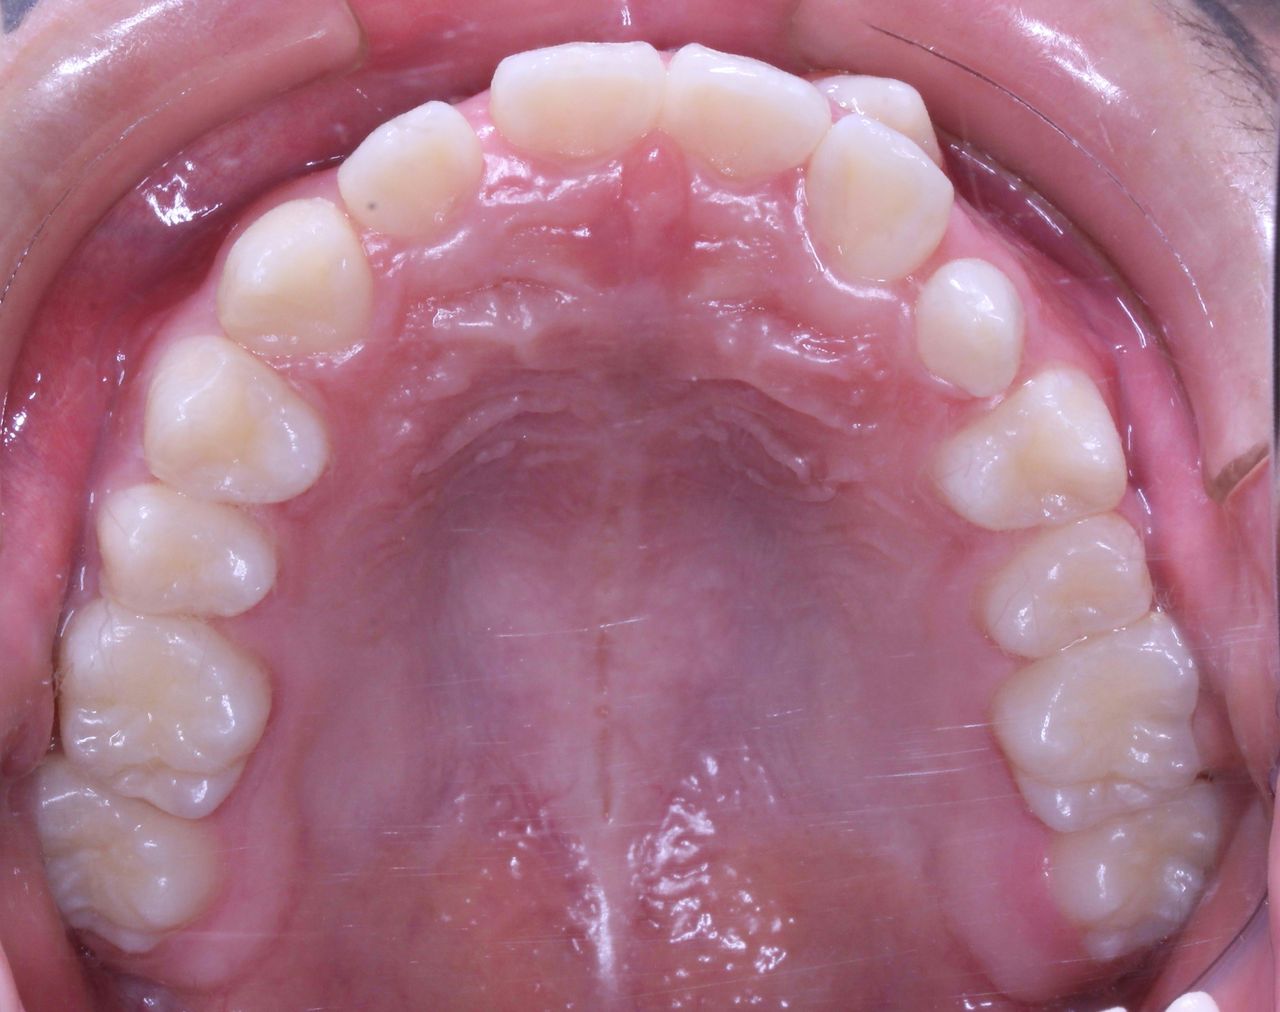

それでは治療開始前の状態です

このように1番目と2番目の歯の間から犬歯3番目の歯が生えてきました。

また乳歯Cが残っているので 歯の順番でいうと

132Cという順番になっております